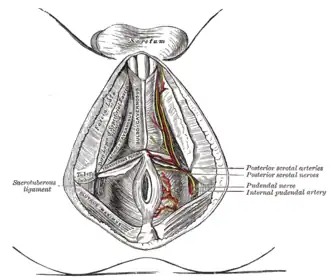

Certaines fibres se prolongent vers la branche de l'ischion pour former le processus falciforme du ligament sacro-tubéral (ou prolongement falciforme du grand ligament sacro-sciatique ou repli falciforme du grand ligament sacro-sciatique). Il contribue au canal pudendal.

Ce ligament ferme en arrière et en bas les petite et grandes incisures ischiatiques qu'il transforme avec la contribution du ligament sacro-épineux en petit foramen ischiatique et grand foramen ischiatique.

Le nerf pudendal peut être piégé entre le ligament sacro-tubéral et le ligament sacro-épineux provoquant une douleur périnéale. La section du ligament sacro-tubéral est une solution pour soulager la douleur.

Articulations du pelvis. Vue antérieure. Les branches superficielles de l'artère honteuse interne.